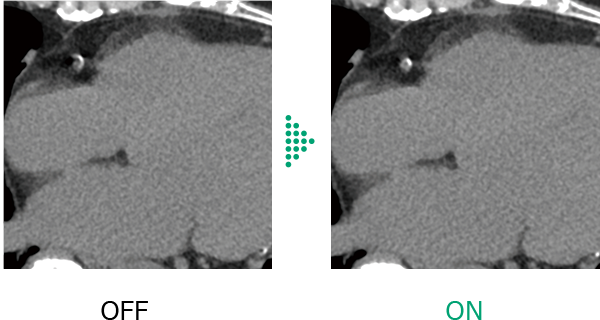

Conventional cardiac CT scans*1 were affected by changes in heart rate during scanning, such as high heart rates and arrhythmias, which affected the image quality of the entire heart and make diagnosis difficult in some cases.

Cardio StillShot*4 calculates the direction and amount of patient motion in four dimensions from the collected raw data and provides images with minimal motion blur due to motion . By applying corrections during image reconstruction, it achieves an effective temporal resolution of up to 28 milliseconds*5.